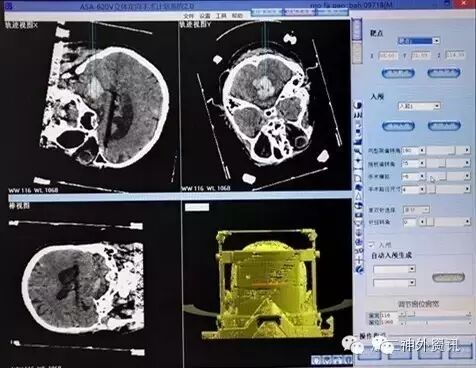

辅助检查: CT:小脑、脑干后部血肿,破入第四脑室及两侧侧脑室后角。按多田氏公式计算血肿量(体积=π/6×长×宽×层面数×层厚)约为20ml(图1)。

图1. 入院CT检查示桥脑出血,血肿约20ml。

手术计划:CT三维图像评估血肿长轴,入颅点选择右枕下中线旁,靶点距离长轴最远端10mm(图3)。

图3. 立体定向手术计划。